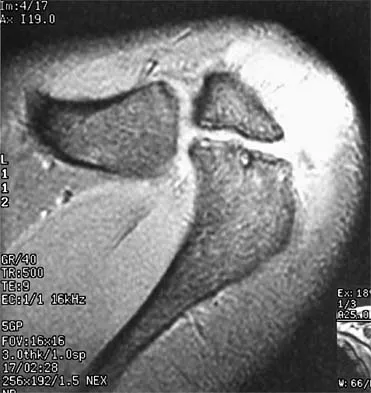

A 39-year-old competitive cyclist sustains an injury to her left hip in a fall. Gadolinium arthrography, with an accompanying MRI scan, is shown in Figure 31. A cleft, or defect, identified by the arrow, indicates a detachment of the